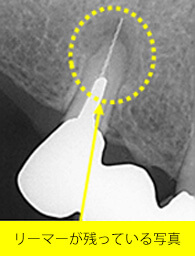

「2.ガス滅菌編」でも書きましたが、歯の根の治療で使用する「リーマー」や「ファイル」といった細い金属の器具がありますが、実は、これが結構な頻度で折れる(※)のです。

原因は、歯科医師の力の入れ具合もありますが、通常の滅菌によって金属疲労を起こしていることが挙げられます。